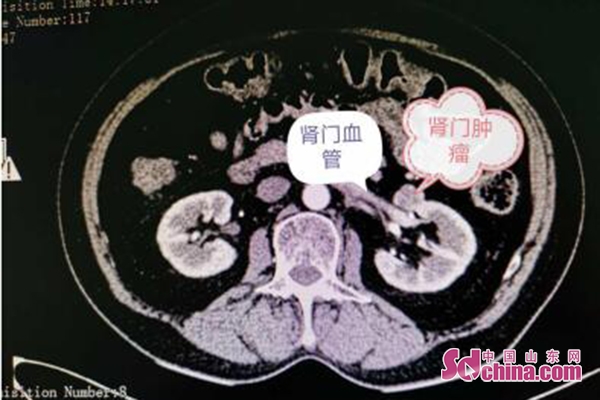

王英磊主任接诊患者后,仔细查体完善相关检查,认真阅片后发现肿瘤位于肾门,与肾静脉紧挨着,肾静脉血管壁像纸一样薄,稍有不慎就会造成大出血,丢肾风险极高。

经与患者及家属详细沟通后,决定制定出适合王女士个体的手术方案:采用经腹腔途径入路,术中将肾动脉、肾静脉精准解剖出来,然后再将肿瘤充分游离、切除、止血,术中未阻断肾动脉,避免了肾脏缺血再灌注损伤,不予缝合则尽量减少肾单位的丢失,可以最大限度的保留肾脏功能。经过周密安排,在手术、麻醉、护理团队的精心配合下,王英磊教授顺利进行了滨医烟台附院首例腹腔镜零缺血免缝合肾部分切除术。